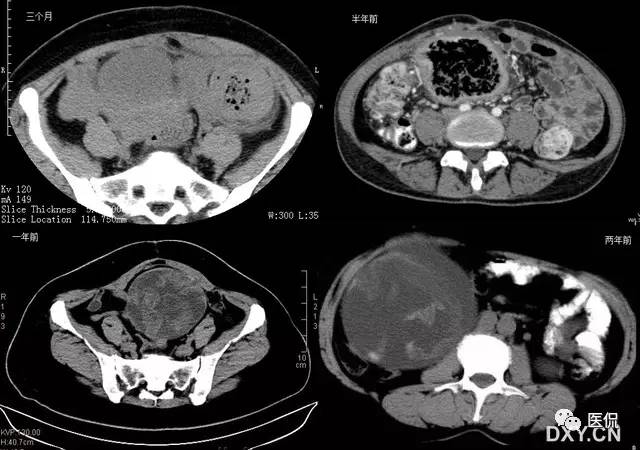

26 蜂窝征

腹腔内残留纱布在人体内引起渗出或液化坏死并纤维包裹形成异物性脓肿(纱布瘤)。纱布瘤的影像特点是:圆形或卵圆形肿块,较大,有完整包膜,薄壁,较少的情况下为后壁,边界较完整,增强后薄膜可以持续强化。不同时期的纱布瘤可以不同的表现:早期(如10各月或半年前)的多表现为蜂窝状;2~5年内一般表现为囊性飘带状;10~20年之后则为实性软策划密度,包膜钙化呈钙化性网状结构。手术过程中残留在人体内的医用纱布所形成的肿瘤样病变。

以下是不同时期纱布瘤的表现: